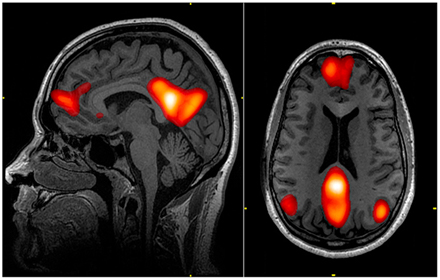

Your automatic thoughts - your thoughts about yourself and the world – your desires and your likes and dislikes are largely the product of the Default Mode Network (DMN). My healing journey didn’t truly begin until I stopped believing what it said.

DMN-Informed Neuroplastic Schema Therapy

Unresolved complex childhood trauma forms a distorted window through which we see the world. DMN-Informed NST is an integrative therapeutic approach that allows the window of your mind to be cleaned - changed - so that the maladaptive habits, that had helped us live with pain, are no longer necessary.